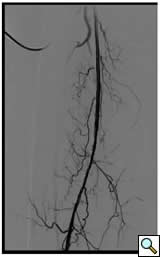

![]() |

Figure 1A: Angiogram |

Case 1: An 84-year-old male with rest pain, who had undergone prior revascularization with covered stents, represents with recurrent rest pain. The prior stents had come close to the origin of the SFA and at that time there had been some narrowing. Exposure was provided by performing a cut down and patching the CFA-proximal SFA to the level of the stents, following which gentle thrombectomy was performed, and a wire passed down. The angiogram demonstrated a distal lesion at the adductor canal which contributed to the thrombosis (Figure 1A). The patient underwent a day of lysis, following which cryoablation was used to treat the distal lesion (Figure 1B) and completion angiogram showed restoration of limb perfusion (Figure 1C).